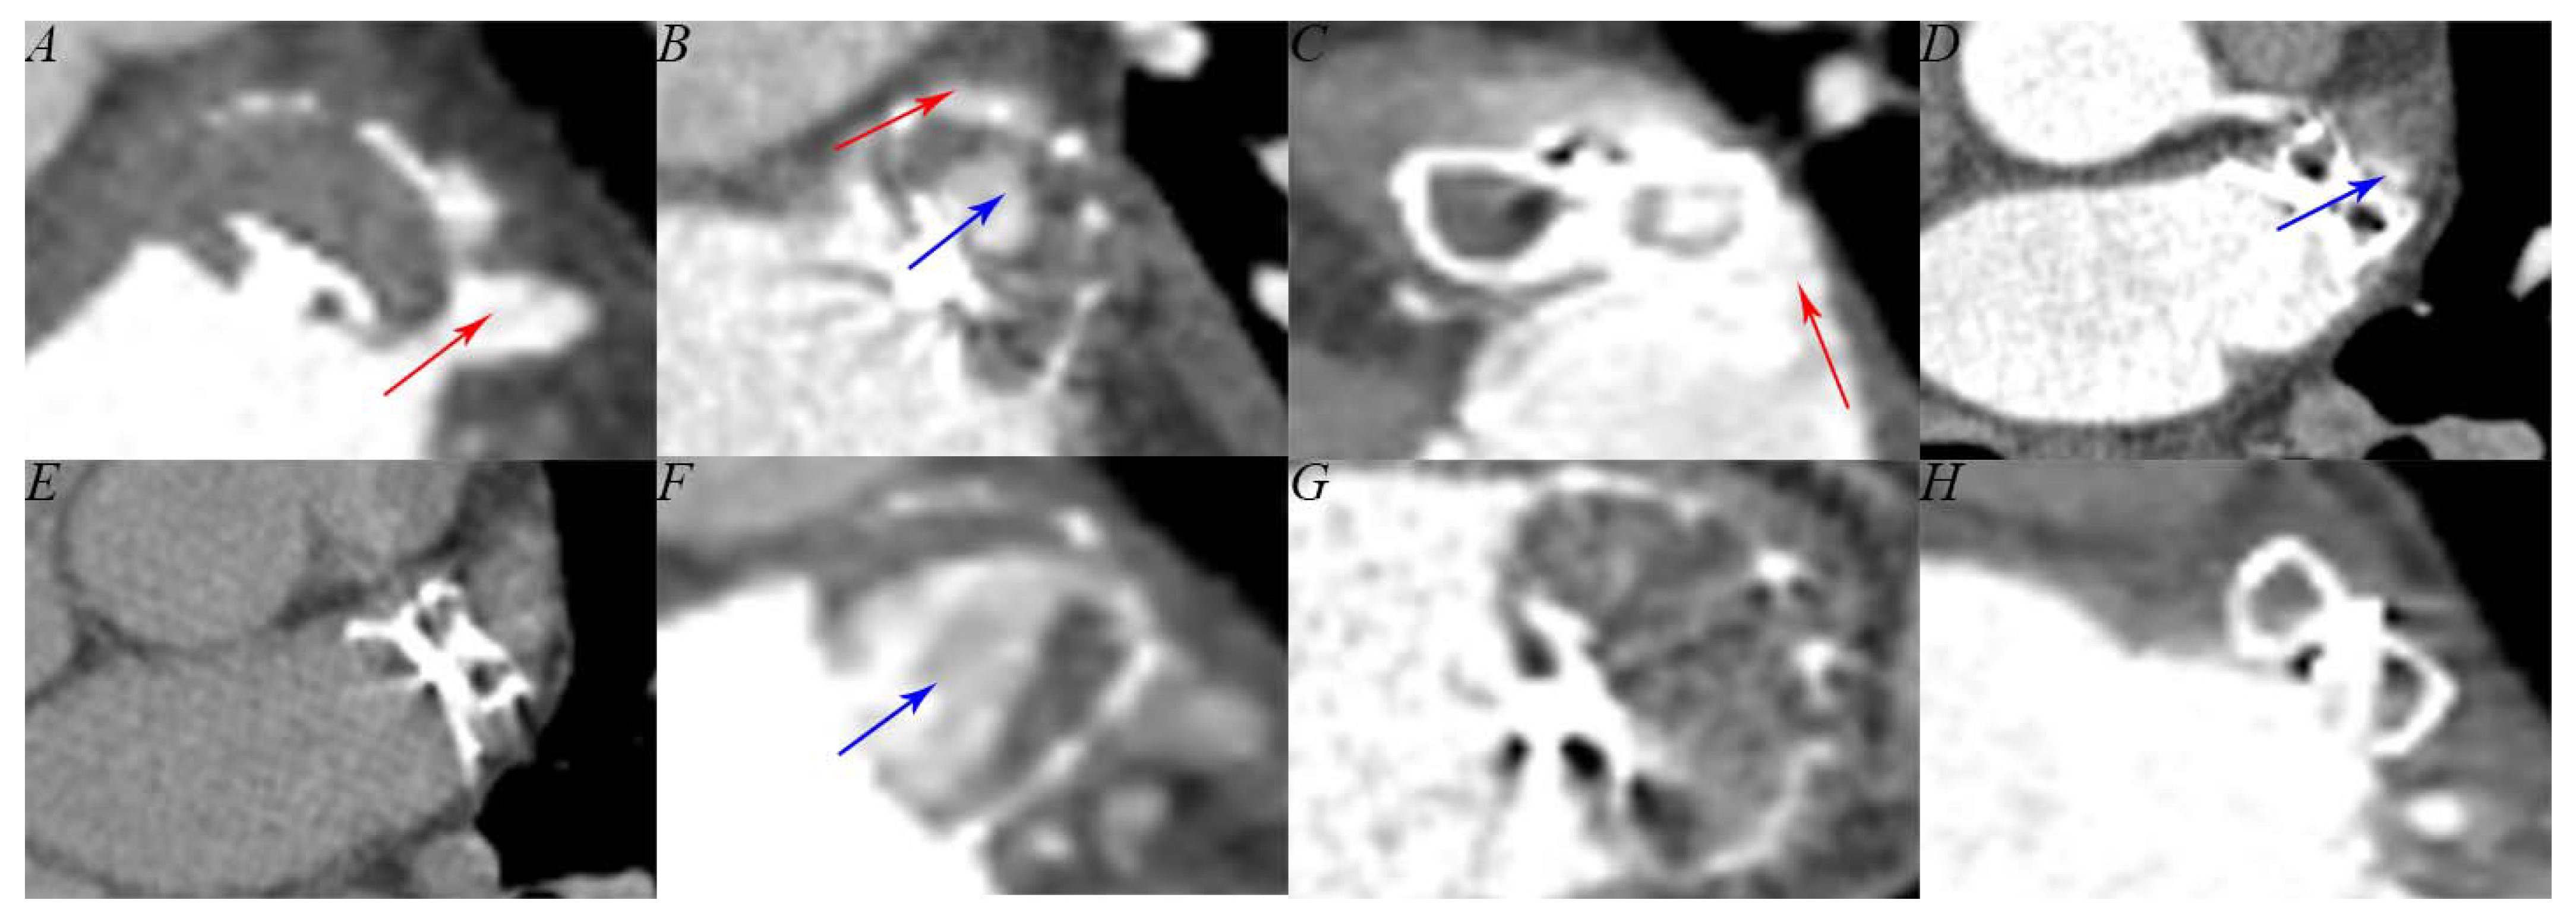

2.4. Computed Tomography Assessment

3.3. Follow-Up Left Atrial Appendage Occlusion Results

4.2. Follow-Up Feasibility